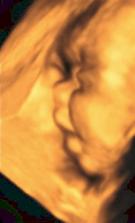

14.10.08 poradna - odebrána krev+moč-výsledky za 14dní, mimísek má 4cm a dostali jsme TĚHOTENSKOU PRŮKAZKU🙂)).............................................27.10.08 poradna - mimísek má 6,5cm, genetický test v naprostém pořádku, riziko se snížilo na 1/9050 - takže téměř žádné-huráááááááá!............................................. 19.11.2008 odběry krve na triplle testy v 16tt - negativní🙂))............................................. 16.12.2008 poradna - vše v pořádku.............................................18.12.2008 velký ultrazvuk - mimísek je v naprostým pořádku, srdčko i všechno ostatní funguje jek má🙂)))............................................. 13.1.2009 poradna + test na cukr............................................. 27.1.2009 poradna - cokrovka je negativní, můžeme mlsat dál🙂............................................. 13.2.2009 4D ultrazvuk-mimísek se nám pořád skovával za ručičky, ale nakonec jsme ho přemluvili a aspoň na chvilku se nám ukázal🙂)............................................. 17.2.2009 poradna- prcek už je hlavičkou dolů a připravenej jít ven, navíc mi strašně tvrdne břicho takže mi dr. zvýšil dávku magnézia a musíme ležet............................................. 2.3.2009 velký ultrazvuk v 31tt - prcek je v pořádku a už má 1700g ............................................. 17.3.2009 poradna - vše ok, prcek má 2100g ............................................. 18.3.2009 sepsání porodopisu ............................................. 26.3.2009 nástup na mateřskou🙂